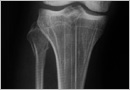

뼈몸통끝(골간단) 연골 이형성증(metaphyseal chondrodysplasia)은 연골내 성장판 부위의 임시 골화층에서 정상적인 무기질화가 이루어지지 않아 성장판이 넓어지고 뼈몸통끝(골간단)이 크고 넓어지는 특징을 갖는 질환입니다.